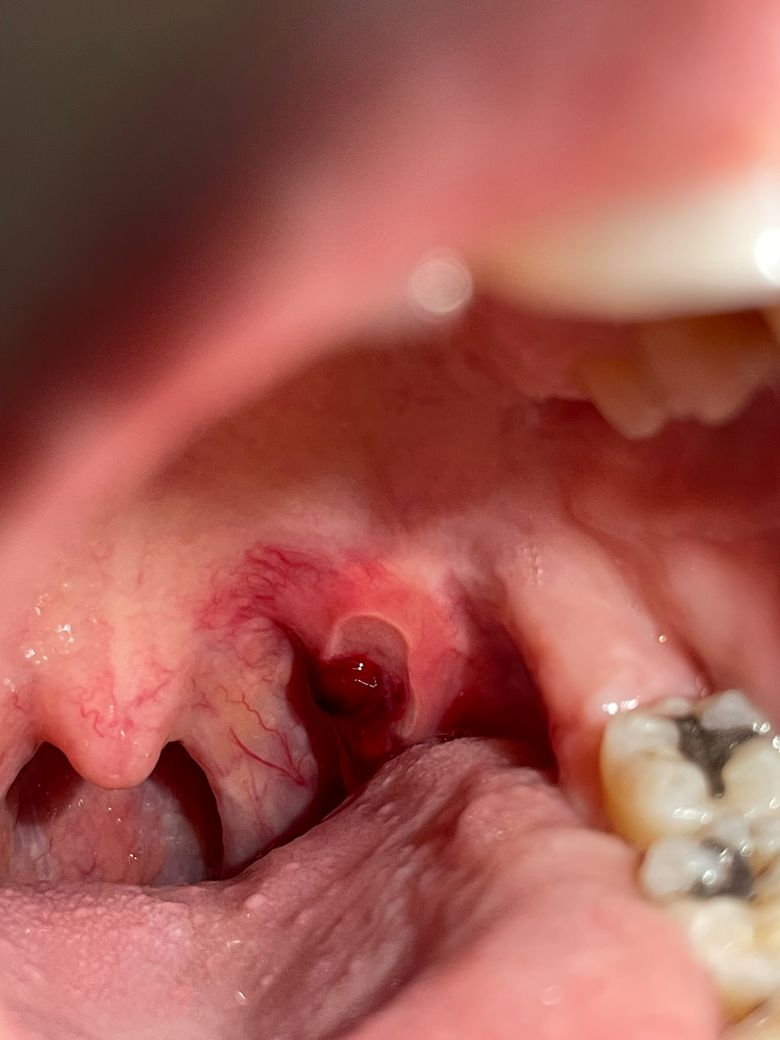

구내염있는 자리에 피고름이 생겼어요

목으로 넘어가는 쪽에 구내염이 크게 생긴지 열흘 정도 되었는데요

침을 삼킬때나 말할때 평소에도 통증이 셉니다

구내염이 자주 생기는 편이라 그냥 뒀는데 오늘은 피고름도 생겨서 걱정이 되네요..

• 1번 째 사진